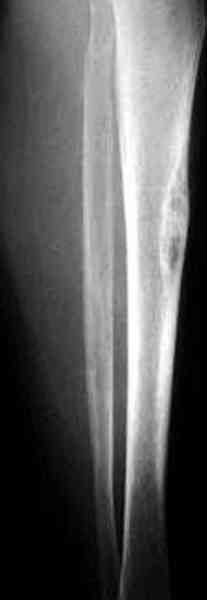

"При его рассмотрении с рентгенологом и морфологом сошлись, что это не фиброзная дисплазия, что было первым предположением по рентгенограммам. В полости было и мягкотканое образование. Окончательно заключение дадут через несколько дней"

По локализации и по характреру опухоли мало напоминает остеобластому, может, представленные биопсийные материалы адамантиномы помогут вашим морфологам дифференцировать опухоль (Basiloid cells, pseudoglandular pattern and peripheral palisading)

К нашему онкологу-ортопеду обратился больной с жалобами на боли в голени, из рассказа - год назад была сделана биопсия большеберцовой кости, но название заболевания "не запомнил”.

В литературе "A Classic Adamantinoma Arising from

Osteofibrous Displasialike Adamantinoma in the Lower Leg: A case report and Review of the Literature похожие снимки.

Снимки представлены.